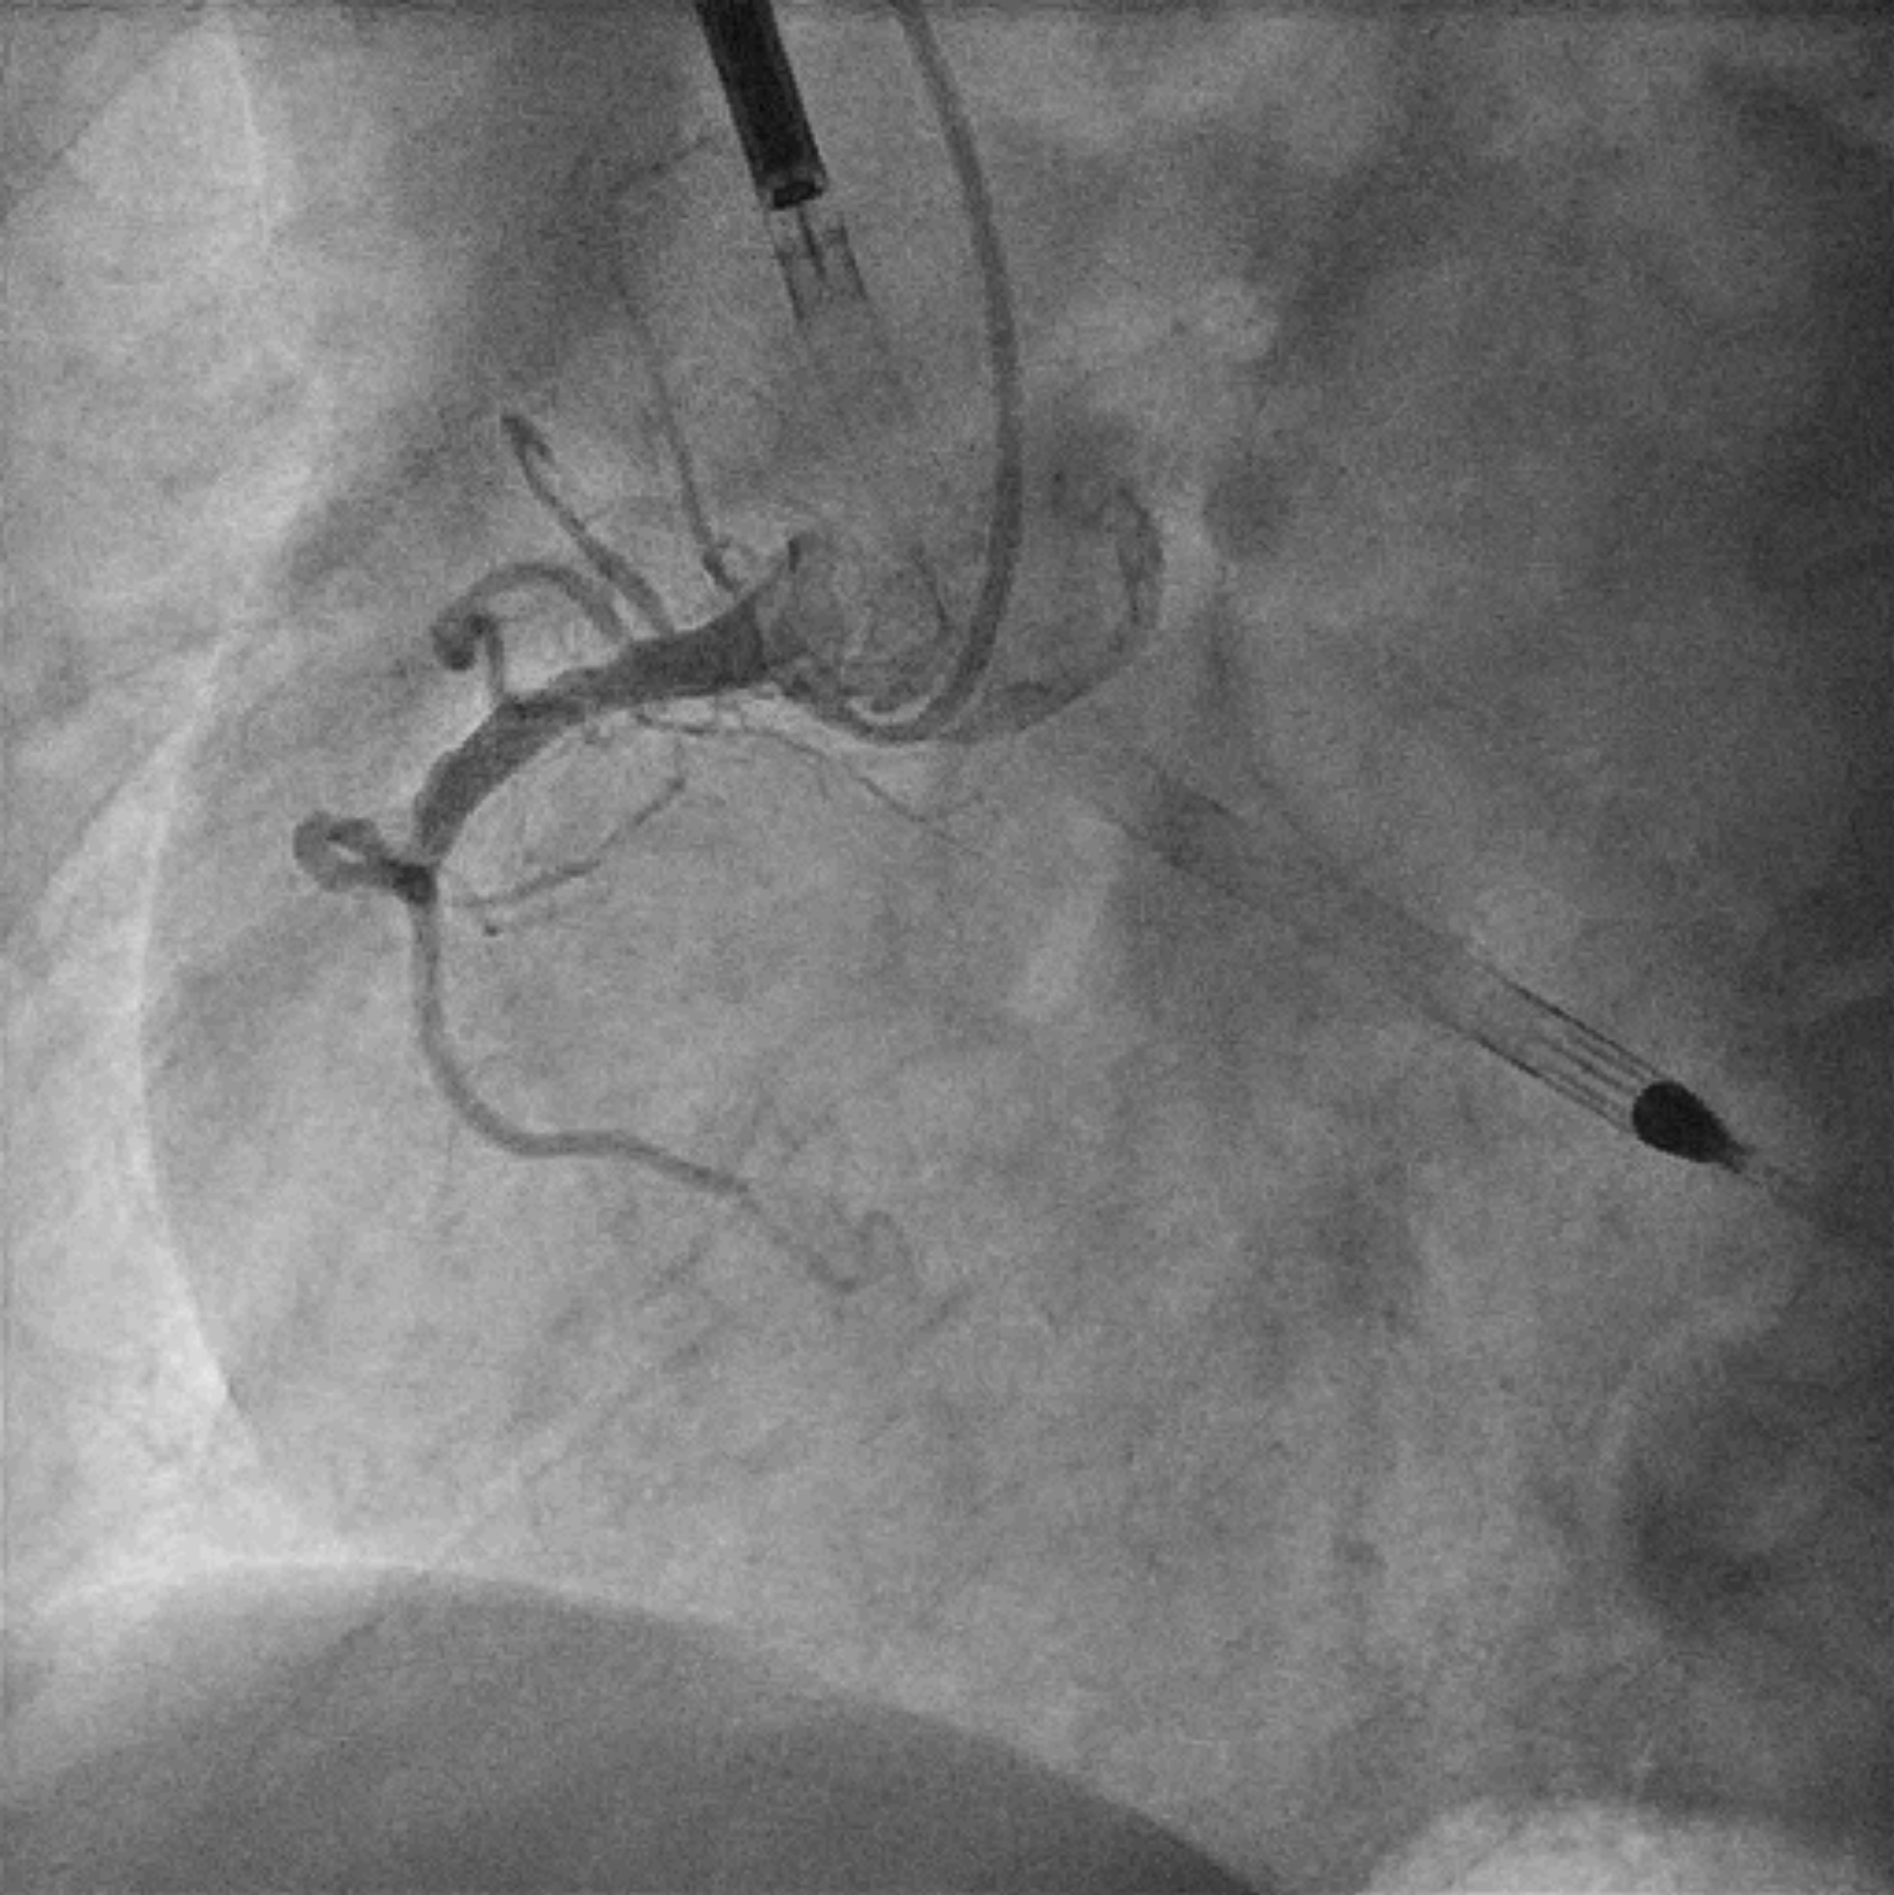

Patient was immediately brought to the catheterization laboratory. During transfer he required escalating inotropic support. LVEDP using a 5Fr pigtail catheter measured 30 mmHg. Coronary angiogram revealed minor disease in LMCA, proximal LAD acute total occlusion, LCx minor disease, proximal RCA total occlusion with no obvious collateral supply.

Left common femoral artery and vein, and right common femoral artery were punctured under ultrasound and fluoroscopy guidance with micropuncture set. Prior to coronary angiogram, Impella was inserted via right common femoral artery into LV. ICU was informed to provide potential ECMO support in the event of further hemodynamic collapse.